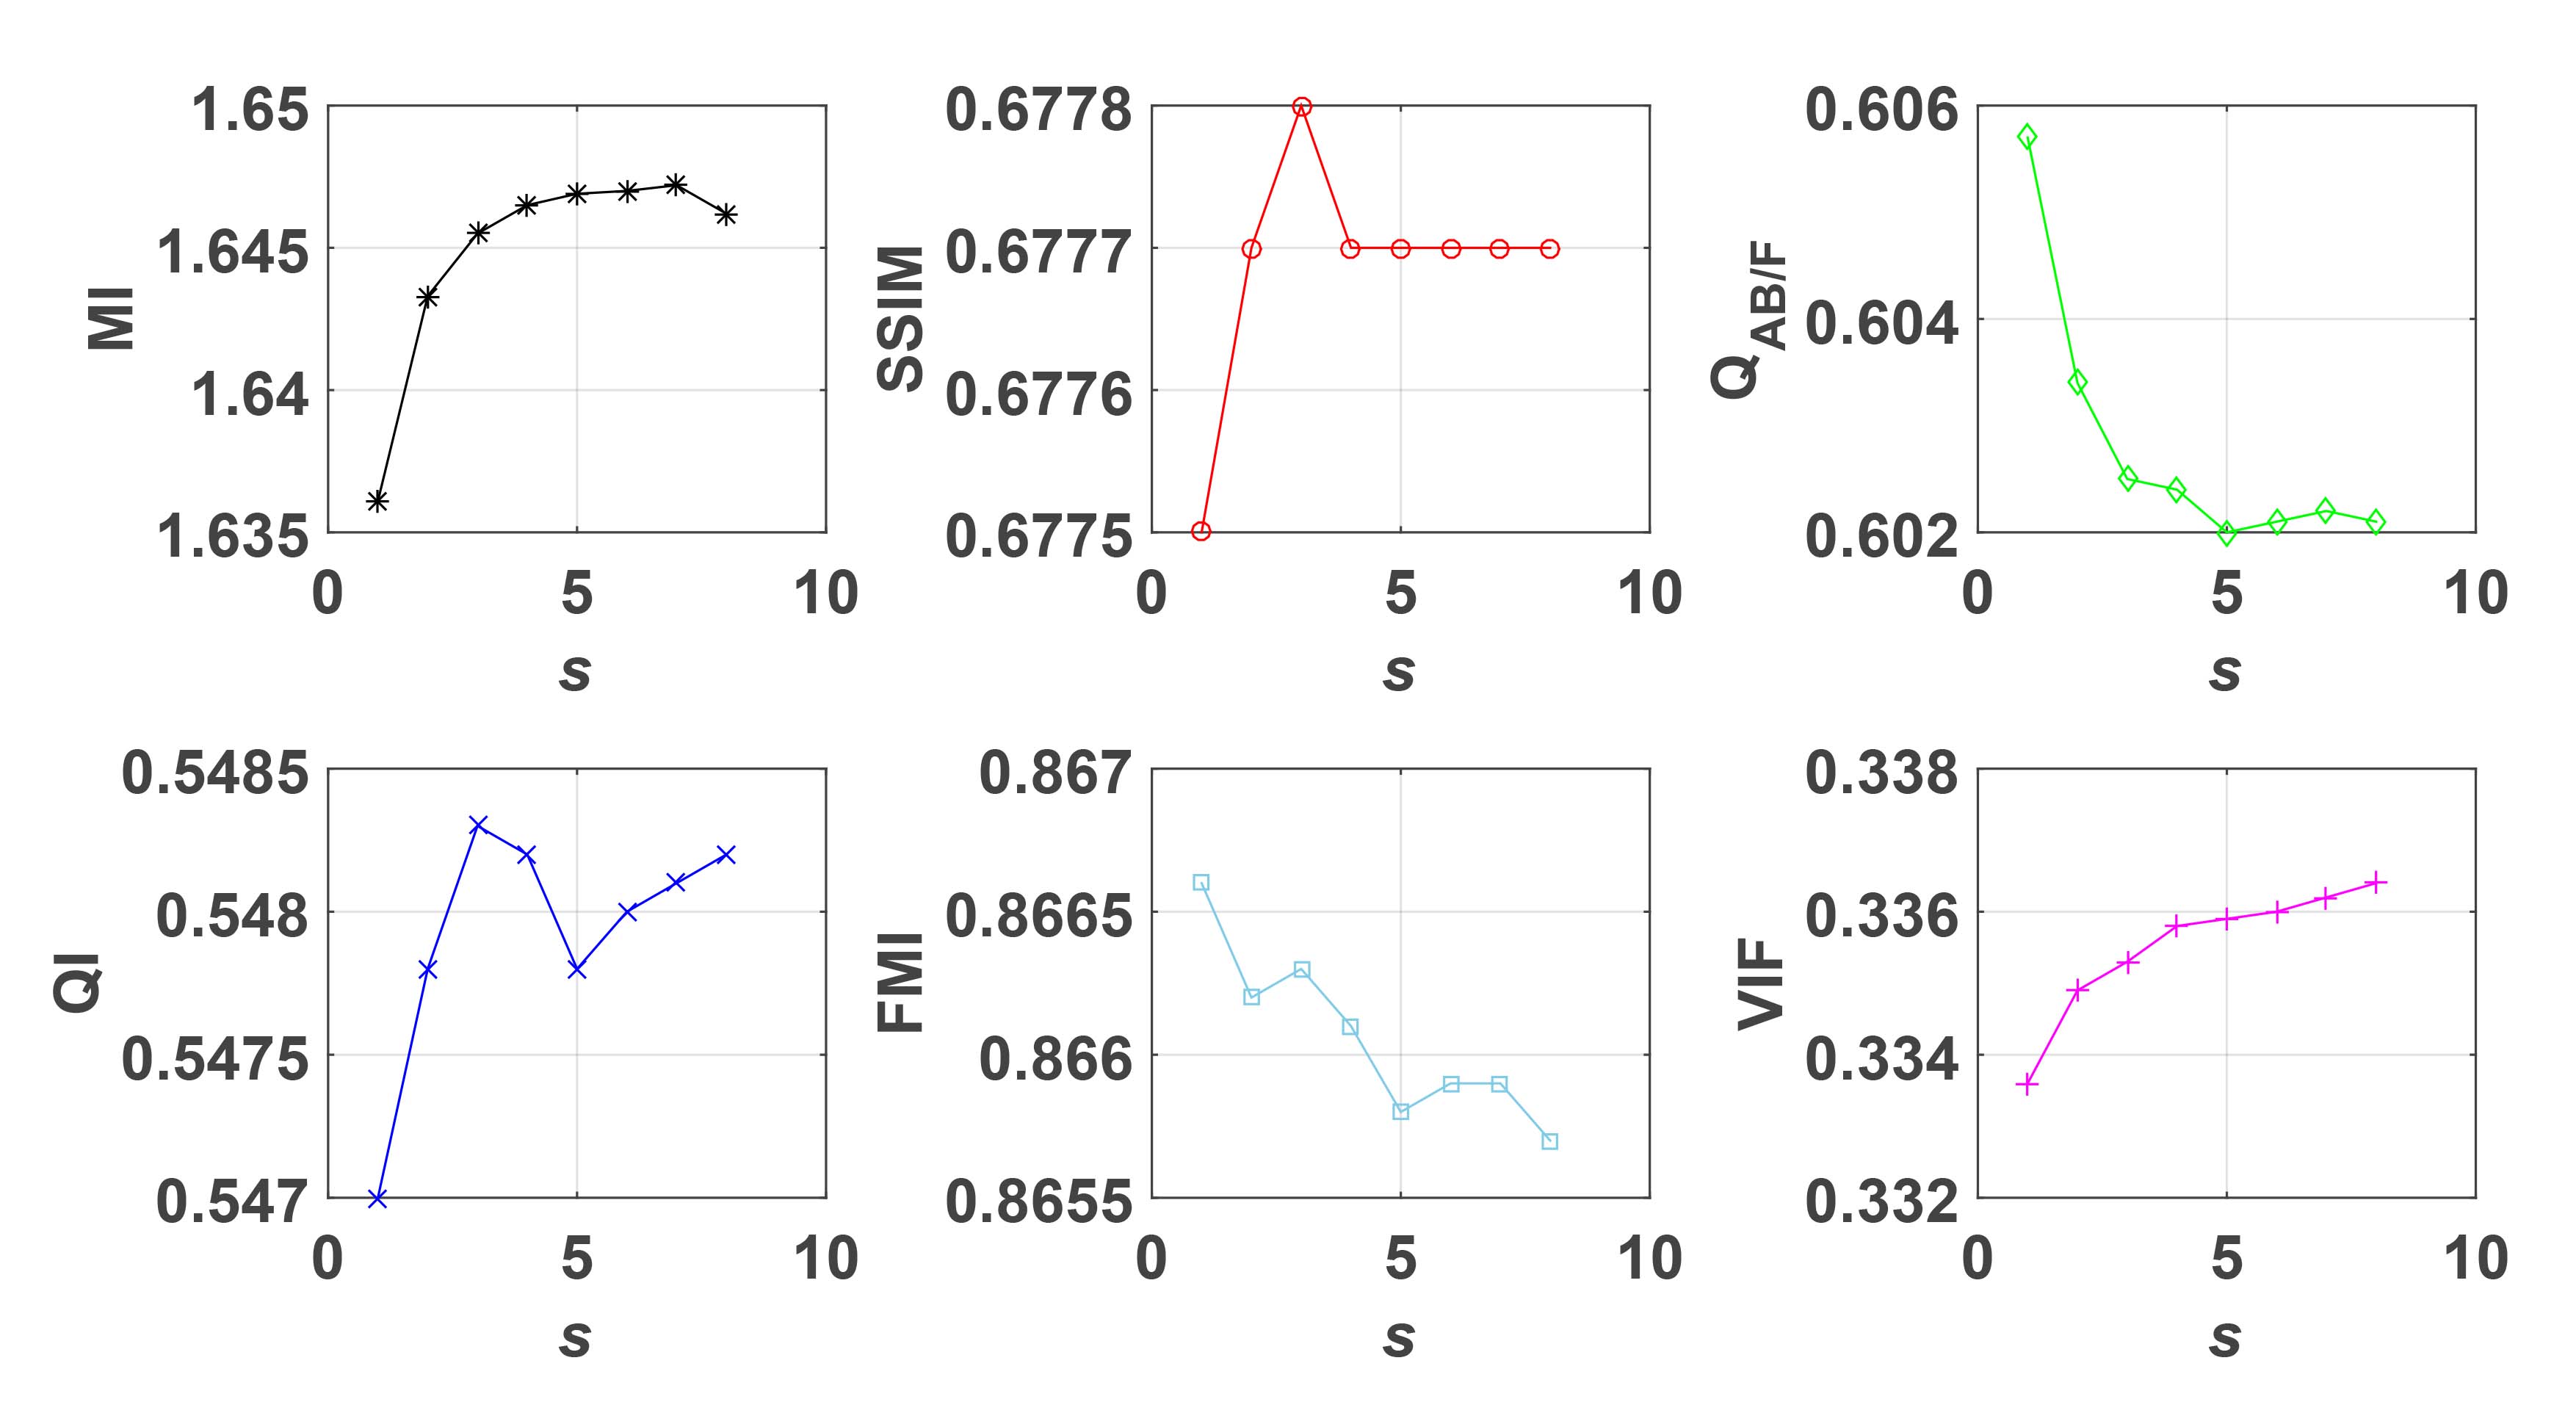

We first evaluate the performance of the proposed method under varying total number of octaves and number of layers sampled per octave. The fused images of a pair of multi-modal medical images with different and are shown in Figure 4. In this example, on the one hand, when only 1 or 2 octaves are involved in constructing the DoG pyramid, the fused images fail to keep the integrity information of large size objects (e.g. eyeballs), while by increasing the value of , the integrity information of eyeballs is preserved. On the other hand, although not as significant as the increase of octave numbers , the fused image can contain more details by the increase of layer numbers . The corresponding objective quality metrics are shown in Figure 5. As shown in Figure 5(a), most of the metric values are improved as the number of octaves increases with the fixed layer numbers 3 in the global tendency and each of them tends to be stable when the number of octaves is 5. To get a relatively good quality from Figure 5(b), we can notice that some of the metric values can get a good performance when the number of layers is 3, such as the MI, SSIM, QI and VIF, though there are only a little change of all the metric values by increasing the number of layers with the fixed octave numbers 5. Because it will result in more computation burden with the increase of the value and , and for different kinds of source images, there are different performance with the diverse parameter settings. To get a trade-off between them in our experiments, we set for the multi-modal dataset, for the natural datasets and for the multi-focus cell dataset, respectively.